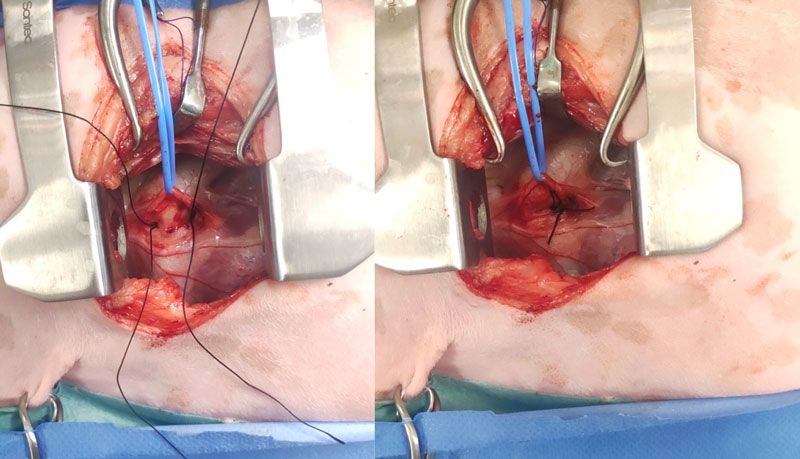

Figure 3: Left fourth intercostal space thoracotomy in a dog with a patent ductus arteriosus. The vagus nerve has been carefully dissected and gently retracted dorsally using a blue vessel loop. A single loop of 2-0 silk has been passed from cranial to caudal medial to the ductus and cut, creating two single strands (left). Starting with the dorsal strand closest to the aorta, both strands are tied slowly and securely, taking care not to break the suture or injure the ductus (right). Cranial is to the left of the images.

Surgical closure: This surgery requires a thorough knowledge of the anatomy of the pertinent vascular, and on the basis of the risk of possible life-threatening haemorrhage, should be performed only by those with extensive surgical experience in this area. Surgical closure should be performed any time from approximately two months of age and ideally before four months of age (Pelosi and Orton, 2018). If diagnosed in older patients, closure should be performed as soon as possible. Patients with pulmonary oedema on thoracic radiographs or significant cardiomegaly and left ventricular dilation on echocardiography may require medical treatment (e.g., diuretics, pimobendan) prior to anaesthesia. Surgical closure involves a left fourth (most commonly) intercostal thoracotomy and tying off the PDA with 2-0 silk (Hunt et al, 2001; Goodrich et al, 2007; Grimes and Thieman Mankin, 2022; McNamara et al, 2023); see Figure 3. A lateral thoracic radiograph can be obtained preoperatively to determine if the left fourth or fifth intercostal space will provide best access to the root of the aorta. A rolled towel can be placed under the thorax to separate the ribs and elevate the heart. A finochietto retractor is used for rib distraction. The left cranial lung lobe is retracted and maintained caudally with a moist swab, exposing the heart. The vagus nerve typically travels over the PDA and is carefully dissected without injury and retracted dorsally or ventrally (Manzoni et al, 2025). Placing a finger over the PDA will identify a thrill. Without opening the pericardium (extrapericardial dissection), dissection of the PDA is performed cranially and caudally with a curved Mixter or Lahey forceps. Initially, dissection should progress vertically on either side of the ductus, followed by around (deep to) the PDA. Great care is taken not to injure the PDA, which could lead to life-threatening haemorrhage. Following passage of a curved forceps from caudal to cranial, a loop of 2-0 silk is grasped between the tips and retrieved caudally. The loop is then cut, creating two strands, one dorsal and one ventral. This technique eliminates the need to pass the forceps twice (Hunt et al, 2001; Manzoni et al, 2025). The suture closest to the aorta is tied first over a period of five-to-10 seconds, making sure to have the suture tight but not break it and potentially injure the ductus. Closure of the PDA can result in a Branham reflex, a decrease in heart rate secondary to an abrupt increase in diastolic pressure (Madruga et al, 2021). Following closure of the PDA, the left cranial lung lobe is returned to a normal position and a swab count performed. A MILA chest drain can be placed to evacuate pneumothorax or air can be removed by means of thoracocentesis. A left apical holosystolic murmur can be auscultated postoperatively in patients with preoperative mitral regurgitation (Bureau et al, 2005).